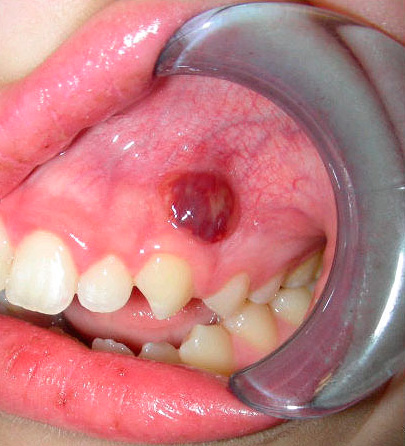

- La parodontite è un'infiammazione dei tessuti che circondano la radice del dente (l'apparato legamentoso che tiene il dente nell'incavo), che si manifesta più spesso con un processo purulento con ingrossamento e gonfiore delle gengive vicino al dente malato o comparsa di fistole sulle gengive, da cui il pus scorre nella cavità orale.